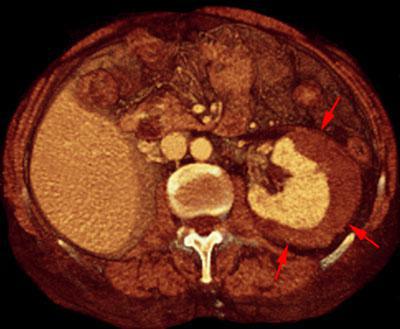

Hematoma subcapsular

VR seccional. Visión axial caudal. Serie contrastada en fase venosa que muestra una inversión de la densidades, visualizándose el hematoma subcapsular (flechas) mas hipodenso que el parenquima renal contrastado